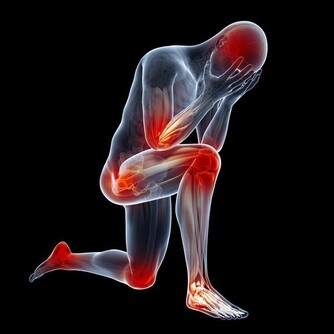

七、在抬腳時,脊椎保持水準,全身肌肉富有彈性,氣血順暢,各關節自會增生骨髓,脊椎兩旁神經恢復平常傳導作用,何來關節退化,或長骨刺?及壓迫神經的病痛呢?